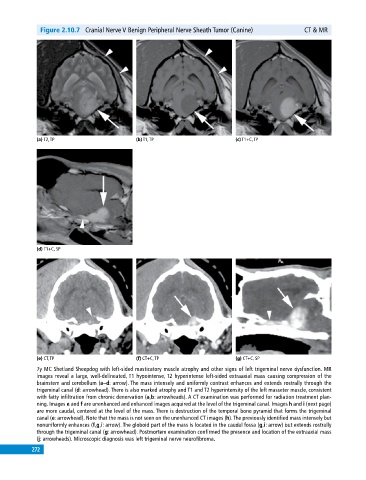

Figure 2.10.7 Cranial Nerve V Benign Peripheral Nerve Sheath Tumor (Canine) CT & MR

7y MC Shetland Sheepdog with left‐sided masticatory muscle atrophy and other signs of left trigeminal nerve dysfunction. MR

images reveal a large, well‐delineated, T1 hypointense, T2 hyperintense left‐sided extraaxial mass causing compression of the

brainstem and cerebellum (a–d: arrow). The mass intensely and uniformly contrast enhances and extends rostrally through the

trigeminal canal (d: arrowhead). There is also marked atrophy and T1 and T2 hyperintensity of the left masseter muscle, consistent

with fatty infiltration from chronic denervation (a,b: arrowheads). A CT examination was performed for radiation treatment plan

ning. Images e and f are unenhanced and enhanced images acquired at the level of the trigeminal canal. Images h and i (next page)

are more caudal, centered at the level of the mass. There is destruction of the temporal bone pyramid that forms the trigeminal

canal (e: arrowhead). Note that the mass is not seen on the unenhanced CT images (h). The previously identified mass intensely but

nonuniformly enhances (f,g,i: arrow). The globoid part of the mass is located in the caudal fossa (g,i: arrow) but extends rostrally

through the trigeminal canal (g: arrowhead). Postmortem examination confirmed the presence and location of the extraaxial mass

(j: arrowheads). Microscopic diagnosis was left trigeminal nerve neurofibroma.